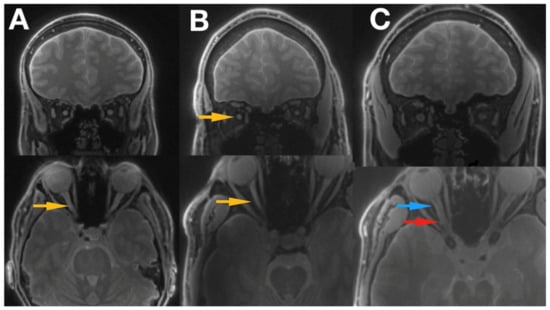

Figure 3.

Shows the images of 2 patients with LHON disease ((A) Idebenone treatment, (B) no treatment received) and a healthy control subject (C). The optic nerve can be easily traced all the way to the optic chiasm, and optic tract is also clearly visible. Blue arrow indicates proximal part of the optic nerve, red arrow the distal part of the optic nerve, and yellow arrows the hyper intensive areas within the optic nerve. LHON, Leber’s hereditary optic neuropathy.

Silent-MT images obtained in a healthy control clearly distinguish the axonal part of the optic nerve and surrounding structures. The optic nerve is clearly visible as well as the surrounding CSF and the optic nerve sheath in the healthy individual. Silent-MT images showed good signal and strong contrast in the optic nerve, had excellent suppression of the fat surrounding the ONSC, and showed no motion artifact. In LHON patients hyperintense areas are visible along the whole optic nerve (Figure 2 and Figure 3). Moreover, the nerve itself looks thinner, with an irregular shape and structure. Abnormalities are mostly visible within the proximal and distal part of the optic nerve as well as within the optic disc area. Moreover, in this work we demonstrate that increasing the number of spokes per group to 192 increases the sequence time efficiency and reduces RF power deposition while maintaining significant MT contrast. There were no adverse events reported in any participant after the scanning.

In this paper, Magnetisation Transfer-weighted Silent (“Silent-MT”) images were evaluated for assessment of the optic nerve and surrounding structures in a cohort of subjects with Leber’s hereditary optic neuropathy. Silent-MT images showed good signal and strong contrast in the optic nerve, had excellent suppression of the fat surrounding the ONSC, and showed no motion artifact. Radiological inspection of Silent-MT images revealed hyper-intense areas along the optic nerve.